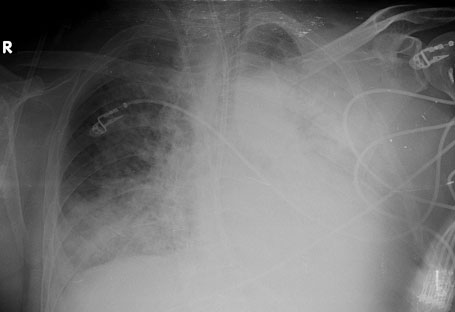

Şekil 2: Tedavinin 3. gününde çekilen PA akciğer grafisi

Tedavinin 3. gününde dispnesi devam eden ancak genel durumu kısmen düzelen hastaya kontrol PA akciğer grafisi çekildi (Şekil 2). 24 saat ara ile alınan 2 adet SARS-CoV-2 PCR sonucu negatif geldi. Kan ve idrar kültüründe üreme olmadı. Anti-HIV negatif geldi. Başlanılan antibiyotik tedavisine de yanıt alınamayan hastada ek tetkik istemeye gerek var mıdır? Var ise mevcut şartlar içinde aşağıdakilerden hangisi veya hangileri en öncelikli seçenek olur.